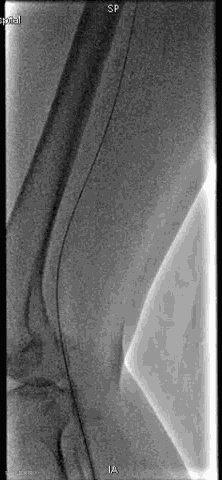

手术过程

抽吸结果